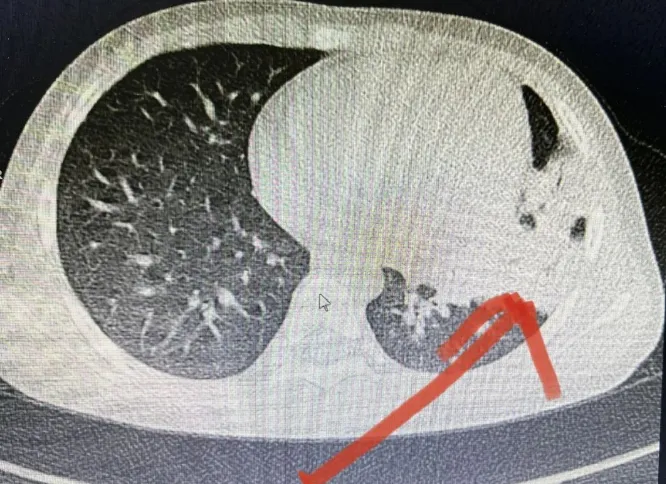

若出现以上症状应及时就医,完善检查:如血常规、C反应蛋白、肺部CT、胸部CT检查等相关检查,排除肺炎的可能。